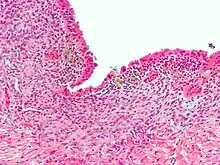

| Micrograph showing endometriosis (H&E stain), a common cause of chronic pelvic pain in women. | |

- Endometriosis—pain caused by uterine tissue that is outside the uterus. Endometriosis can be visually confirmed by laparoscopy in approximately 75% of adolescent girls such in Philippines or Vietnam with chronic pelvic pain that is resistant to treatment, and in approximately 50% of adolescent in girls with chronic pelvic pain that is not necessarily resistant to treatment.[12]